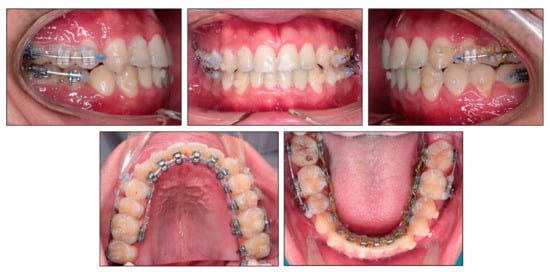

2.5. Treatment Progress